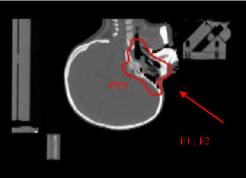

The strategy followed in the nominal treatment (PLAN-NOM) was to draw safety volumes around the metallic rods and to apply hard dose constraint to such volumes of interest (VOIs), as shown in Fig.2, such that the pencil beams of the four fields (F1, F2, F3, F4) involved in the treatment were safe from hitting the rods.

Figure 2: Patient with metallic cage: nominal IMPT dose distribution; inside the patient volume, the green contour corresponds to the PTV and the red ones to the OARs; otuside the patient volume, the safety VOIs and the effective countours of the 4 metallic rods are visible; the fields F1, F2, F3, F4 used for PLAN-NOM and PLAN-OL-1 are also shown.